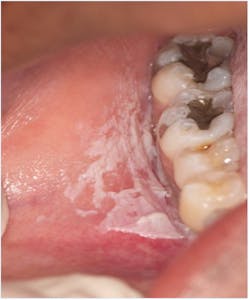

Oral candidiasis

Oral candidiasis (figure 4) is a fungal infection caused by Candida albicans that occurs secondarily to immune suppression. The most common oral form, acute pseudomembranous candidiasis, presents as a white, red, or mixed-color lesion. Findings occur in ages ranging from infants through seniors and immunocompromised populations. Most often, oral candidiasis is displayed as a white patch that can be “easily removed with gauze.”5 This is a key sign that helps distinguish this lesion from others. Candidiasis lesions are often asymptomatic and can be found on the tongue, labial and buccal mucosa, gingiva, hard and soft palates, and the oropharynx. Sometimes symptoms include a burning sensation, bleeding, and changes in taste perception. Initial treatment includes oral antifungal pastilles such as nystatin.5